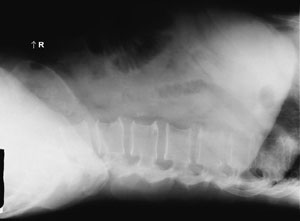

The position demonstrated in the abdomen image below is the:

- Dorsal decubitus

- Erect lateral

- Lateral decubitus

- Ventral decubitus

Dorsal decubitus

The abdomen image below could be improved by:

1. Directing the

CR to the level of the iliac crest

2. Decreasing mAs

3.

Decreasing kV

- 1 only

- 3 only

- 1 and 2 only

- 2 and 3 only

1 only